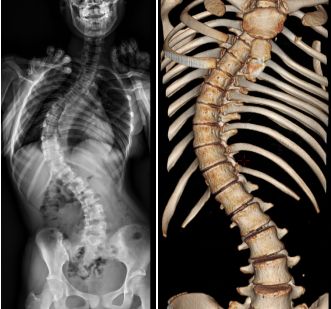

青少年特发性脊柱侧凸是一种尚不明确病因的脊柱结构性的侧凸。为青少年期特发性疾病,其中 60%~80% 的患者都是女孩。

因其发病初期较隐匿,不易被发现,所以 10~16 岁儿童中只有 2%~3% 可察觉到脊柱侧凸。大多数患者在病情中后期症状明显时或体检时发现。

主要临床表现为:脊柱明显弯曲、双肩不等高、剃刀背、前胸不对称等。AIS 严重影响青少年身心发育,身材失去了美丽,后期严重影响心肺功能。

如下图:

脊柱侧弯